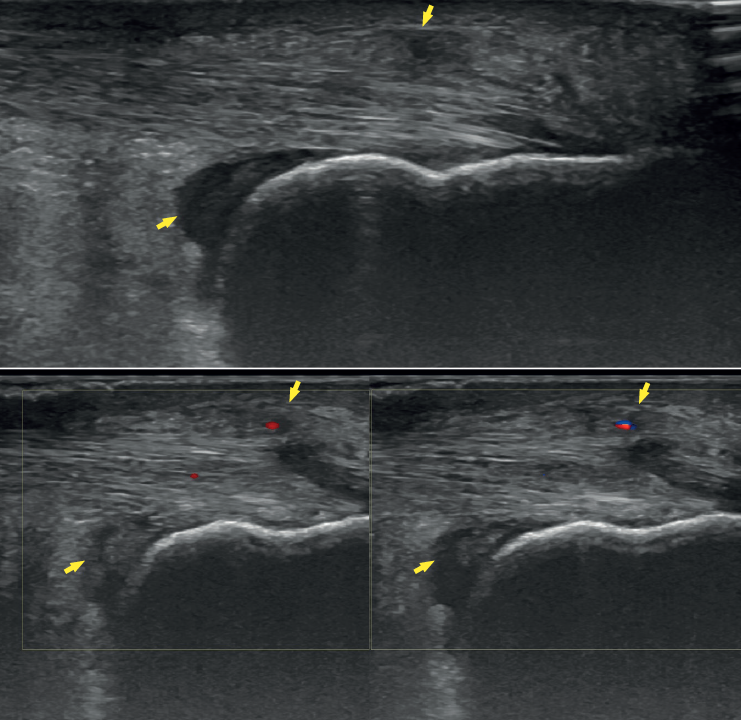

Ultrasound

Ultrasound allows us to identify inflammatory signs in both bursae, tendon lesions and bone exostosis. Tendon degeneration is characterised by poorer echogenicity (a lower mean value on the scale of greys), due to the lesser organisation and altered composition of the tendon microstructure(21). Doppler ultrasound in turn allows us to assess neovascularisation zones (Figure 4). Ultrasound offers dynamic exploration and is operator-dependent.

Figure 4. Ultrasound exploration. Retrocalcaneal bursitis and signs of tendinopathy (yellow arrows). Doppler ultrasound allows the identification of tendon hypervascularisation areas.